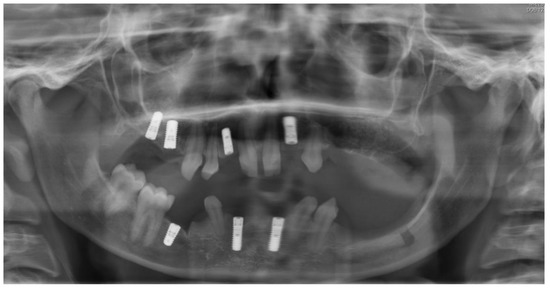

Figure 7.

Initial panoramic radiography.

Figure 6.

Intraoral situation after orthodontic treatment and extraction of deciduous teeth.

A 25-year-old patient attended the Dental Clinic of Hospital University Münster about the unattractive smile and limited function. Anamnesis revealed an ectodermal dysplasia, which was confirmed genetically. No history of medication or allergy was given. Intraoral and radiological examination showed a permanent tooth agenesis, permanence of primary dentition and reduced vertical dimension. The interdisciplinary treatment included presurgical orthodontic treatment for teeth alignment and increase in vertical dimension, coronoplasty of anterior teeth, followed by implant placement at the sites 13, 23, and 25 and rehabilitation with implant-supported crowns.

At the time of implant planning, orthodontic treatment was already finalized. Dental implants were planned to replace missing teeth at sites 13, 23, 36, 45, 46. Despite adequate teeth alignment, wide interproximal spaces at sites 13 and 23 revealed the need of combined restorative and surgical treatments (Figure 6 and Figure 7). Thus, dental implantation in the upper jaws was associated with enlargement of lateral incisors and correction of form in the case of teeth 13, 23.